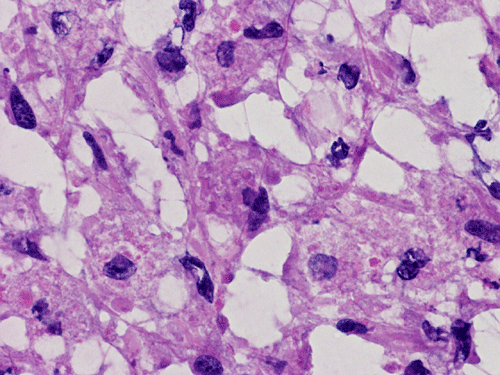

He was admitted again. In this admission, he developed left intraparenchymal hemorrhage associated with the enhancing mass, edema, and 0.4 cm left to right midline shift. A craniectomy was performed to evacuate the blood and biopsy the enhancing mass. The followings are representative images from the biopsy material.

![]() |

H. Frozen |

I. Frozen |

J. Frozen |

K. |

L. | M. | N. |

Panel A to E are intra-operative cytologic preparation, Panel E to J are frozen section, Panel K to N are permanent sections.